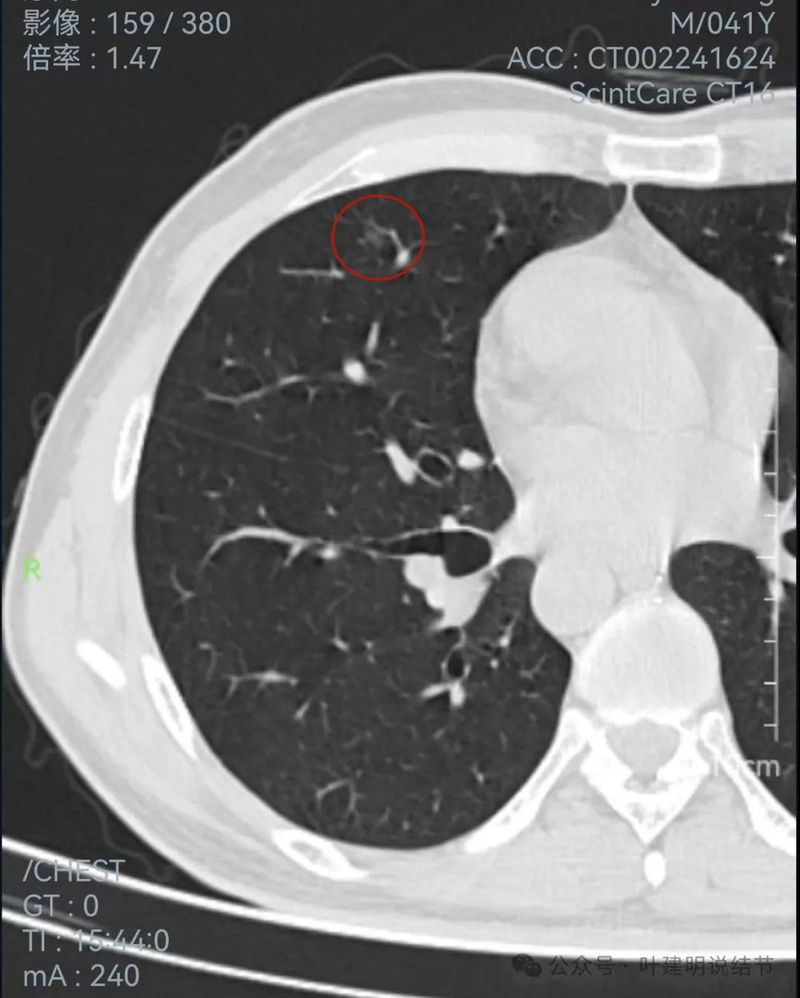

左侧病灶连续层面:

2024年1月靶重建:

病灶密度较高,有月牙铲征,轮廓显模糊。

有微小血管,密度较高,有偏实性成分,磨玻璃密度淡,边界稍糊。

似乎密度过高,毛刺不是太锐利。